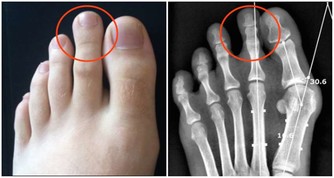

四.單側流鼻涕難以擤出,鼻孔不通氣,睡覺打呼嚕,乃是鼻息肉的信號。